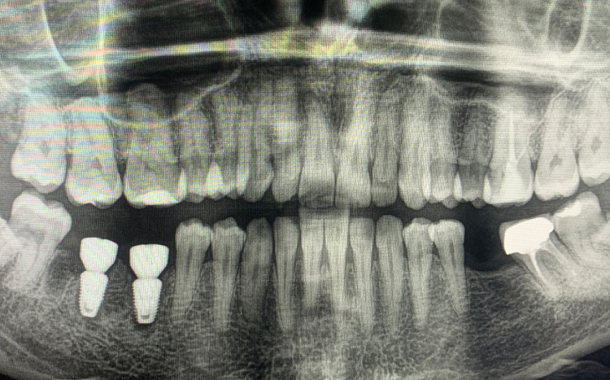

Применение Indiba после стоматологических процедур, таких как удаление зубов, костная пластика и имплантация, обеспечивает ряд значительных преимуществ:

- Улучшение приживаемости имплантатов: усиление кровоснабжения в области имплантации способствует лучшей интеграции имплантата с костной тканью.